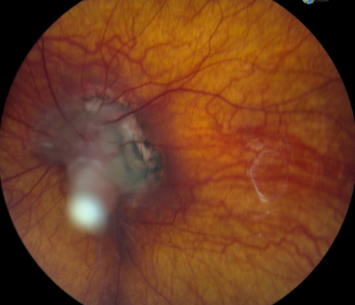

PHPV/PFV

PHPV